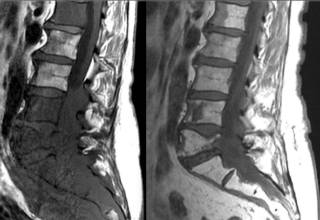

Остеома

Остеома – доброкачественная опухоль, которая образуется из костной ткани. Для этой патологии характерен медленный рост, отсутствие выраженных симптомов. Хотя болевые ощущения могут присутствовать даже на начальной стадии развития заболевания. Остеома редко перерастает в злокачественную опухоль.

Остеома — доброкачественная опухоль костной ткани — способна вызывать боль даже в начальной стадии

При значительном увеличении часто сопровождается болью, искривлением позвоночника, сдавливанием вертебральных сегментов.

Остеобластома — довольно редкое заболевание. Относится к доброкачественным образованиям. Имеет схожесть с остеомой, но отличается быстрым ростом и крупными размерами области поражения.

Иногда шишка на позвоночнике между лопаток говорит об остеоме. Возникает из костной ткани. В 85% — это дети и молодежь не старше 25-летнего возраста.

Причины появления:

Больные чувствуют постоянную боль на спине, в том месте, где локализовалось новообразование. Может развиться сколиоз, проблемы с чувственностью и двигательной активностью при разрастании остеомы.

Болезненное уплотнение на спине у позвоночника лечат оперативно. После удаления опухоли больной полностью выздоравливает.